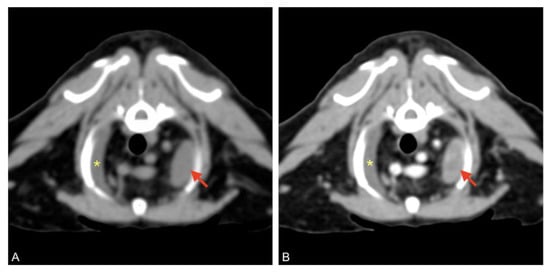

After the patient had been stabilized with pericardiocentesis, a CT scan was performed with a 16-slice CT scanner (GE Brightspeed®, General Electric Healthcare, Milano, Italy); whole body images were acquired before and after intravenous administration of non-ionic iodinated contrast media (iodixanol 320 mgI mL−1, at a dose of 2 mL kg−1). The CT scan revealed severe, homogeneous, non-enhancing, pericardial effusion (12 HU) and mild right pleural effusion that caused severe ventral lung compression. A cranial mediastinal mass was identified close to the thoracic wall, left-sided, localized at the level of the second intercostal space, ellipsoid-shaped (1 × 1.4 × 1.4 cm), with well-defined margins, soft tissue attenuation, and heterogeneously enhanced (Figure 4 and Figure 5).

Figure 4. Pre (A) and post-contrast (B) images of the left-sided cranial mediastinal mass (red arrows), adjacent to the thoracic wall, ellipsoid-shaped, and heterogeneously enhanced. Mild pleural effusion is visible on the right (asterisk).